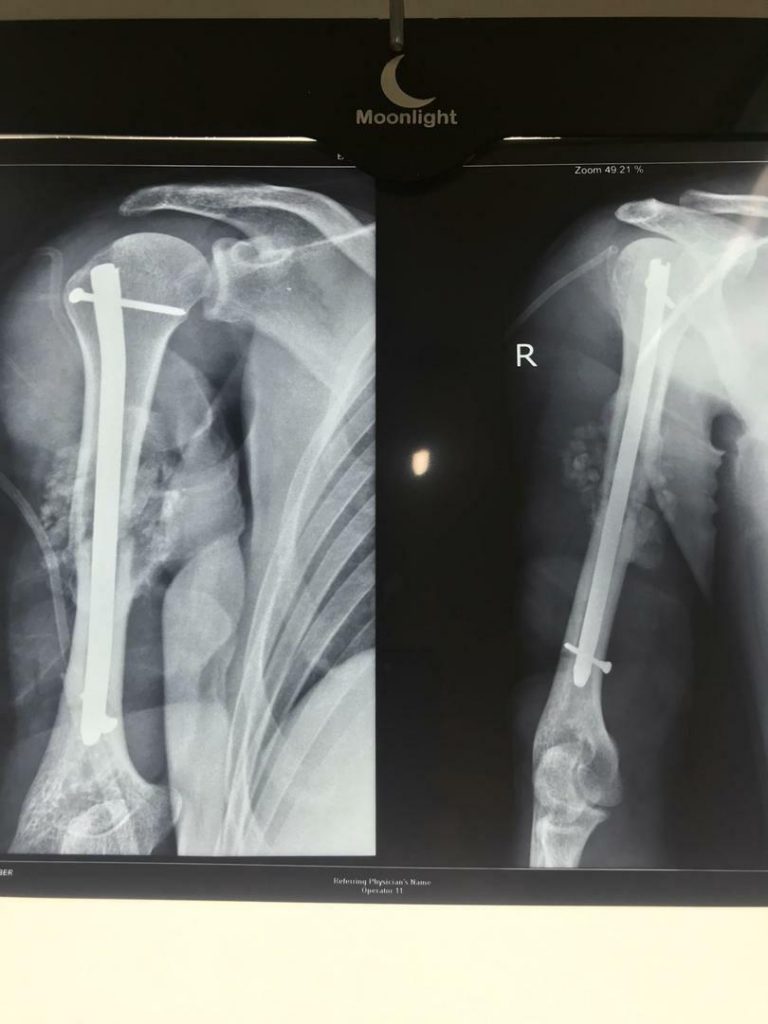

جراح ارتوپدی و شکستگی

درصورتی که شدت آسیب وارد شده به مفصل به گونه‌ای باشد که با سایر روش‌های درمانی آسیب برطرف نشود، جراح ارتوپد عمل تعویض مفصل را برای درمان توصیه می‌کند. با این عمل، بخشی یا همه محل آسیب دیده مفصل با پروتز جایگزین می‌شود. عمل تعویض مفصل به طرز قابل توجهی درد مفاصل آسیب دیده را کاهش می‌دهد، موجب بهبود توانایی حرکتی مفصل و کاهش مشکلات حرکتی فرد و به طور کلی باعث بهبود کیفیت زندگی فرد می‌شود.

انواع عمل جراحی‌ تعویض مفصل یا آرتروپلاستی، با توجه به نوع مفصل عبارتند از: عمل تعویض مفصل زانو، عمل تعویض مفصل لگن و ران، عمل تعویض مفصل شانه، عمل تعویض مفصل آرنج و عمل تعویض مفصل مچ پا.